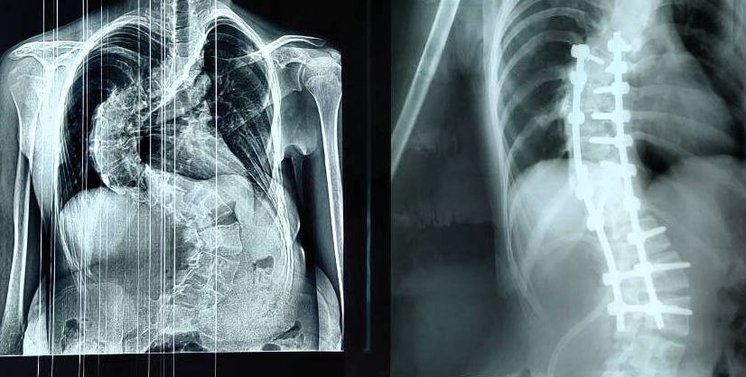

В кировский Центр травматологии обратилась 14-летняя девочка с тяжелейшей формой грудопоясничного сколиоза. Позвоночник девочки был деформирован до формы латинской буквы S.

Сложную высокотехнологичную операцию по коррекции деформации позвоночника провел врач-травматолог-ортопед Дмитрий Курдюмов, который занимает пост первого зампреда правительства региона. Операция длилась 4 часа.

Мы установили многоопорную винто-стержневую систему: в позвонки последовательно введены специальные импланты – транспедикулярные винты, по вогнутой и выпуклой стороне деформации установлены отмоделированные титановые стержни. Перед нами стояли непростые задачи – выпрямление позвоночника и сохранение его функций. Всё, что планировали, мы выполнили. Девочка получила возможность жить полноценной жизнью. Благодарю операционную бригаду и всех коллег, – поделился Дмитрий Курдюмов.